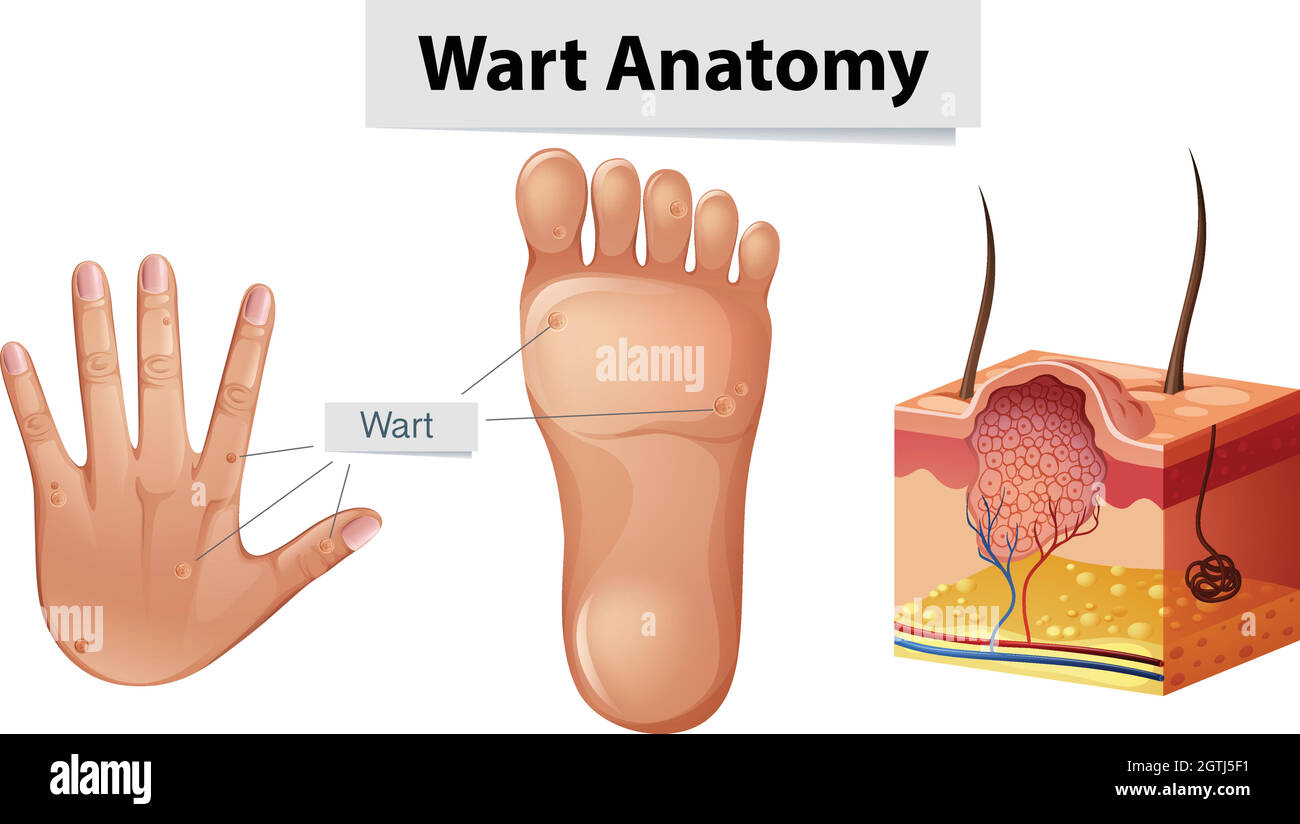

RF2DGMY46–Les verrues du pied sont causées par une infection par un type de virus du papillome humain. Gros plan du HPV